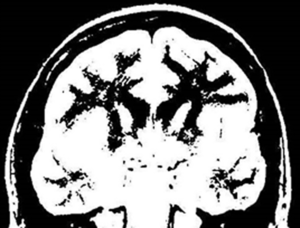

写真1のMRI画像を見てください。これは脳の断面図で、黒く太い木の枝のように見えるのが、発達した神経細胞から伸びる神経線維の集まりで「白質(」はくしつ)と呼ばれます。この神経細胞同士を結び付ける「枝ぶり」こそ脳の個性です。